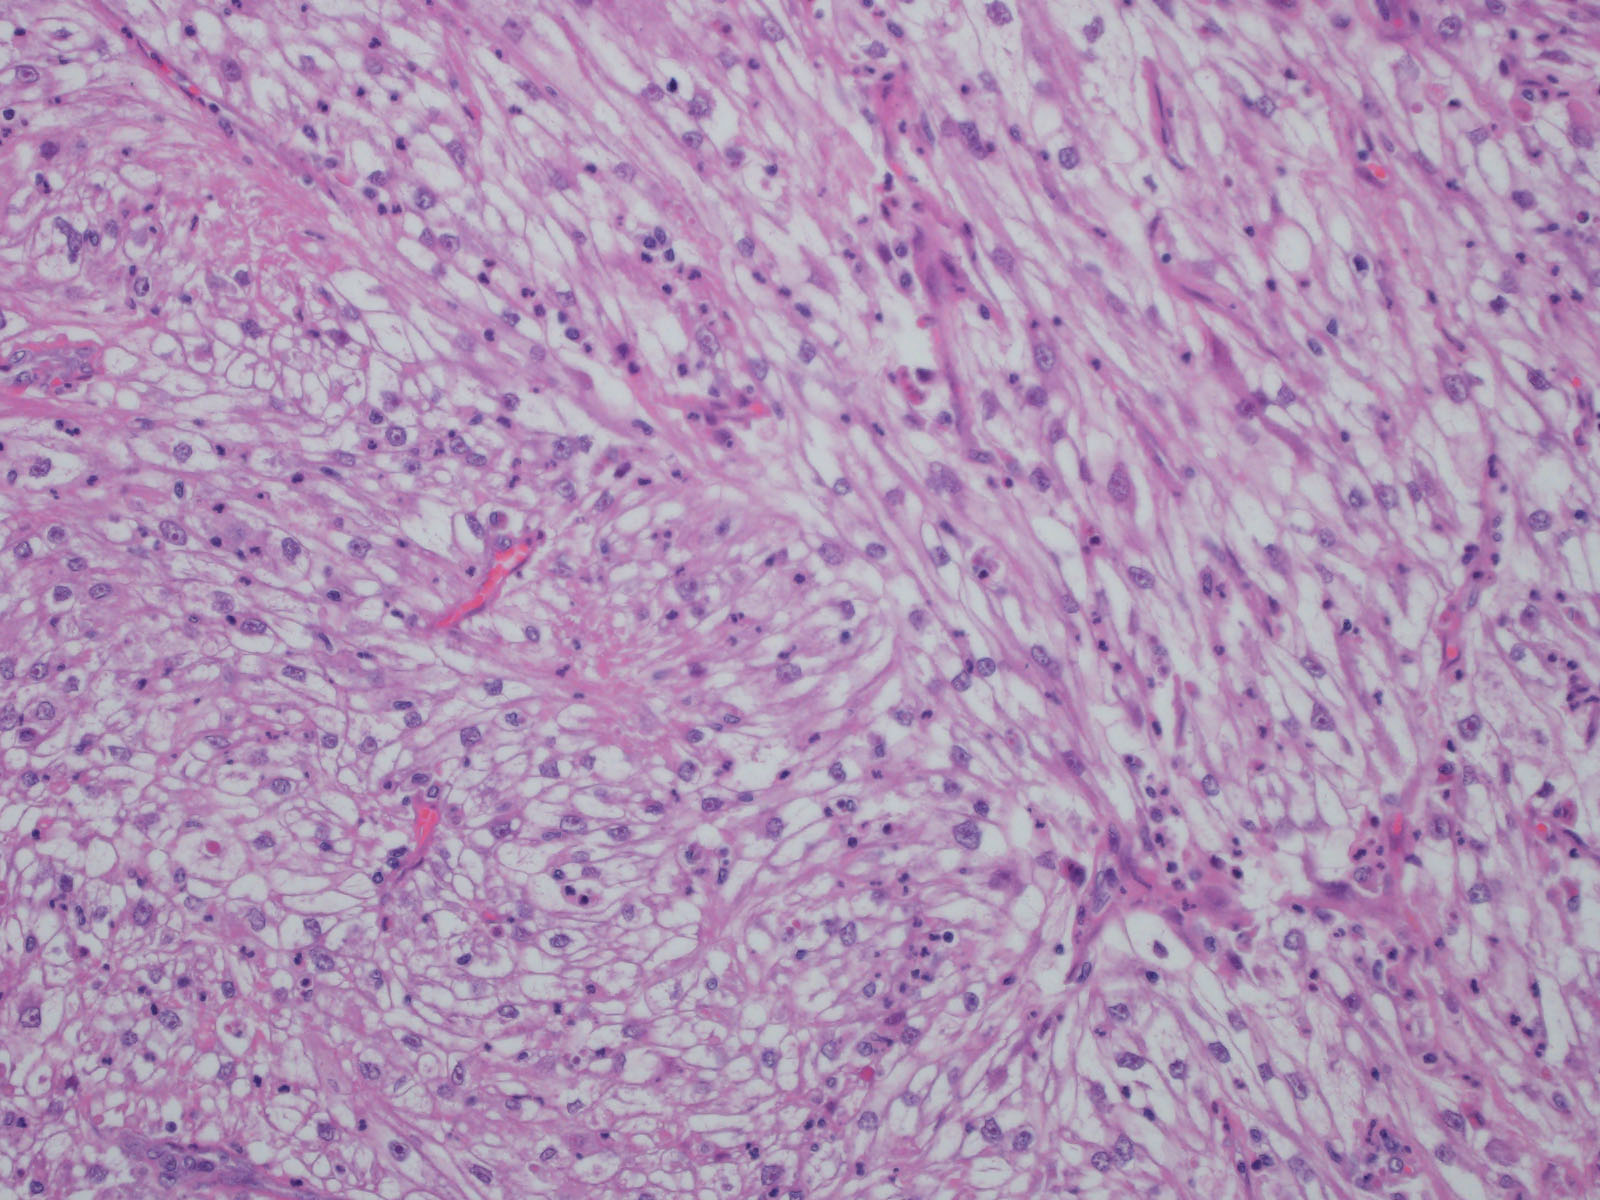

Consensus grade: Clear cell RCC

Show diagnosis by expert panel members| User | Diagnosis | Difficulty | Comment |

|---|---|---|---|

| Pathologist 1 | Clear cell RCC | Typical | |

| Pathologist 2 | Clear cell RCC | Typical | |

| Pathologist 3 | Renal cell carcinoma, unclassified | Not typical |

Could be a clear cell but not sure |

| Pathologist 4 | Clear cell RCC | Not typical | |

| Pathologist 5 | Clear cell RCC | Typical |

with sarcomatoid differentiation |

| Pathologist 6 | Clear cell RCC | Typical | |

| Pathologist 7 | Clear cell RCC | Typical |

sarcomatoid |

| Pathologist 8 | Clear cell RCC | Typical |

| Pathologist 9 | Insufficient tumor for diagnosis | Not typical | |

| Pathologist 10 | Clear cell RCC | Typical | |

| Pathologist 11 | Clear cell RCC | Not typical | |

| Pathologist 12 | Clear cell RCC | Not typical | |

| Pathologist 13 | Clear cell RCC | Not typical | |

| Pathologist 14 | Clear cell RCC | Not typical | |

| Pathologist 15 | Clear cell RCC | Typical | |

| Pathologist 16 | Clear cell RCC | Typical | |

| Pathologist 17 | Clear cell RCC | Not typical | |

| Pathologist 18 | Clear cell RCC | Not typical |